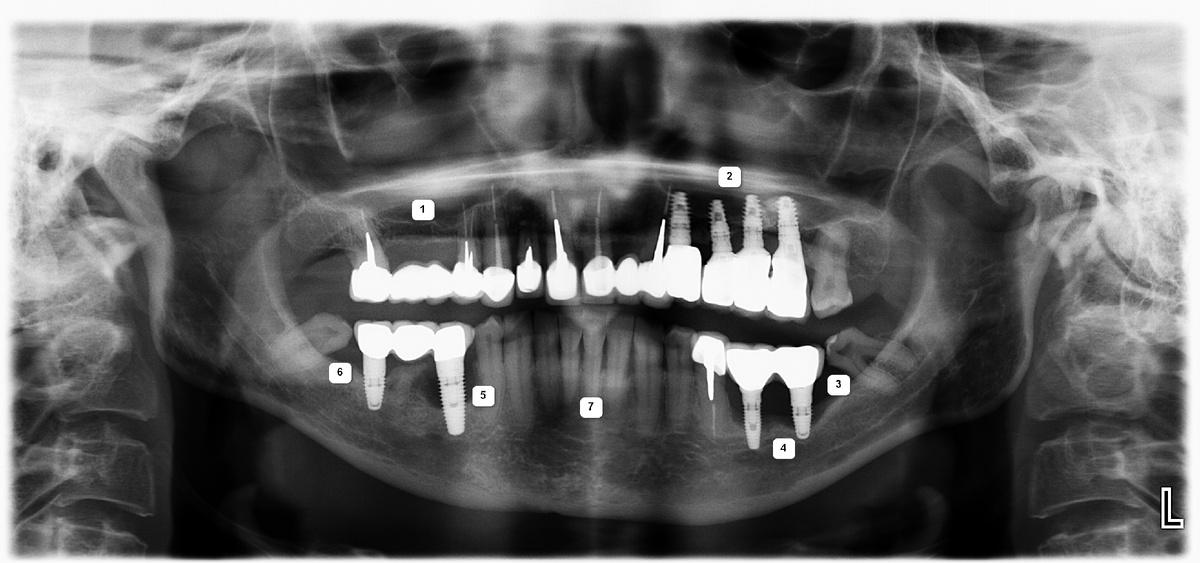

На рентгеновском снимке ситуация в полости рта выглядит следующим образом:

Проблемы:

1 — атрофия костной ткани в области ранее удаленных 5 и 6 зубов на верхней челюсти справа.

2 — атрофия костной ткани до первого витка имплантов в области 4, 5 и 6 зубов на верхней челюсти слева

3 — внушительный «карман» между зубом мудрости и коронкой на импланте, проведение гигиены которого в домашних условиях было невозможно

4 — выраженная атрофия костной ткани, убыль десны, оголение имплантатов, воспаление, гноетечение

5 — экстремальная атрофия костной ткани в области импланта 5-ого зуба, воспаление мягких тканей, гноетечение

6 — симметричный «карман» слева, между зубом мудрости и коронкой на импланте

7 — клиновидные дефекты (абфракции) и закономерная рецессия (опущение) десны

Позитив:

Сохранившиеся зубы во фронтальном отделе, и снизу, и сверху, подарили нашей героине последний шанс восстановить зубы без искусственной розовой десны